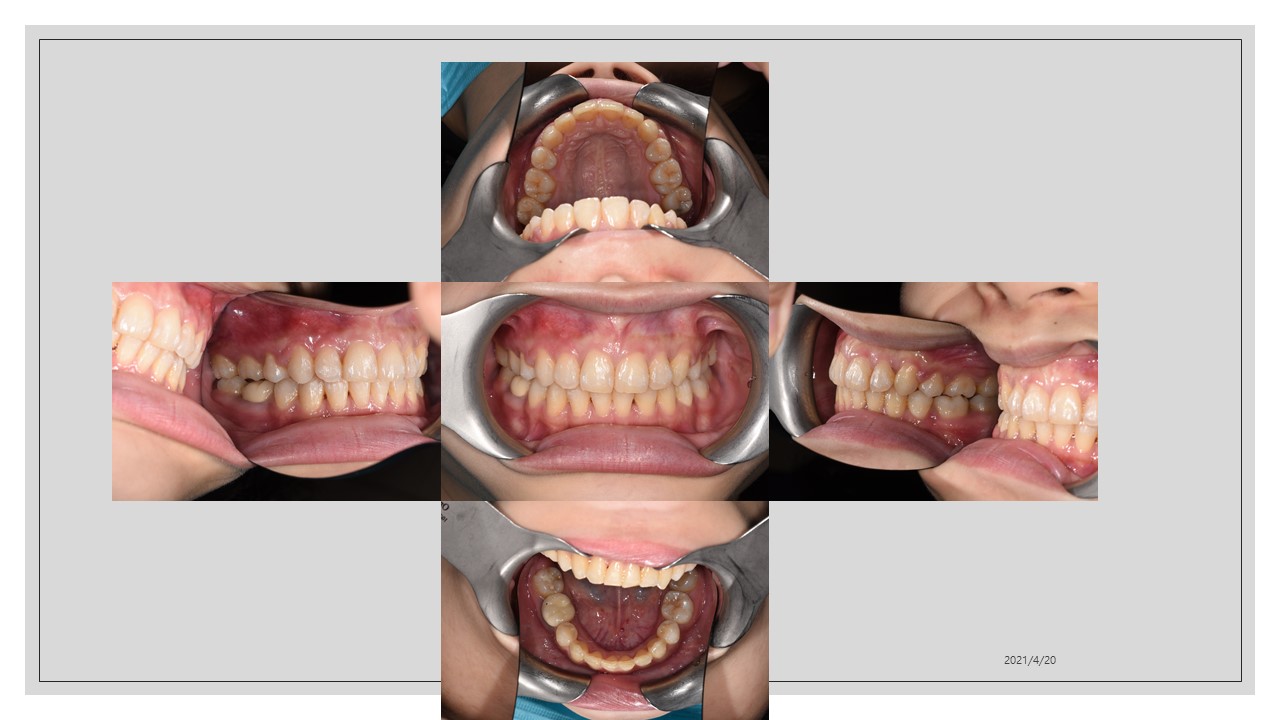

牙齒矯正|牙齒凌亂矯正

適應症:咬合不正